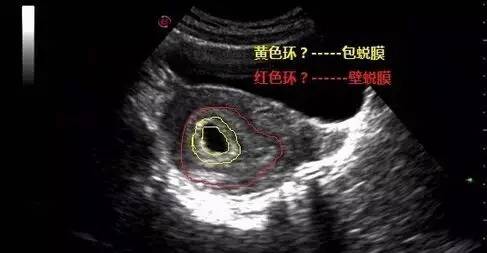

二、双蜕膜征(亦称双环征double-ring sign)

为宫内孕囊与相邻子宫蜕膜结构的断面图像,属于宫内早期妊娠的重要征象。可以用于和异位妊娠的单蜕膜征(单囊征)或假孕囊(pseudo-sac)的鉴别。早孕合并出血时,此征更显著(呈"C"形无回声区),通常预后良好。

双环征是指着床过程中发生少量出血,致使子宫包膜与壁蜕膜分离。它在早孕超声鉴别诊断中具有很重要价值。

双环征妊娠5~8周,妊娠囊周围的高回声绒毛形成内环,外周有一低回声的外环,称双环征。外环可能是包蜕膜与真蜕膜之间的暗区,也有认为外环是由低回声的蜕膜形成,约60%妊娠有此征象。